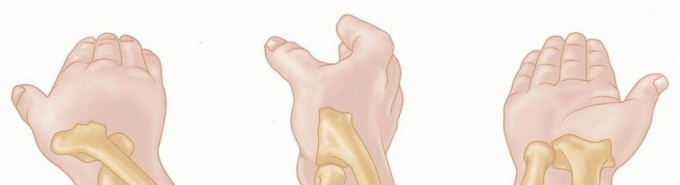

Volar Plating of Distal Radius Fractures Volar Plating of Distal Radius Fractures DEFINITION Distal radius fr…